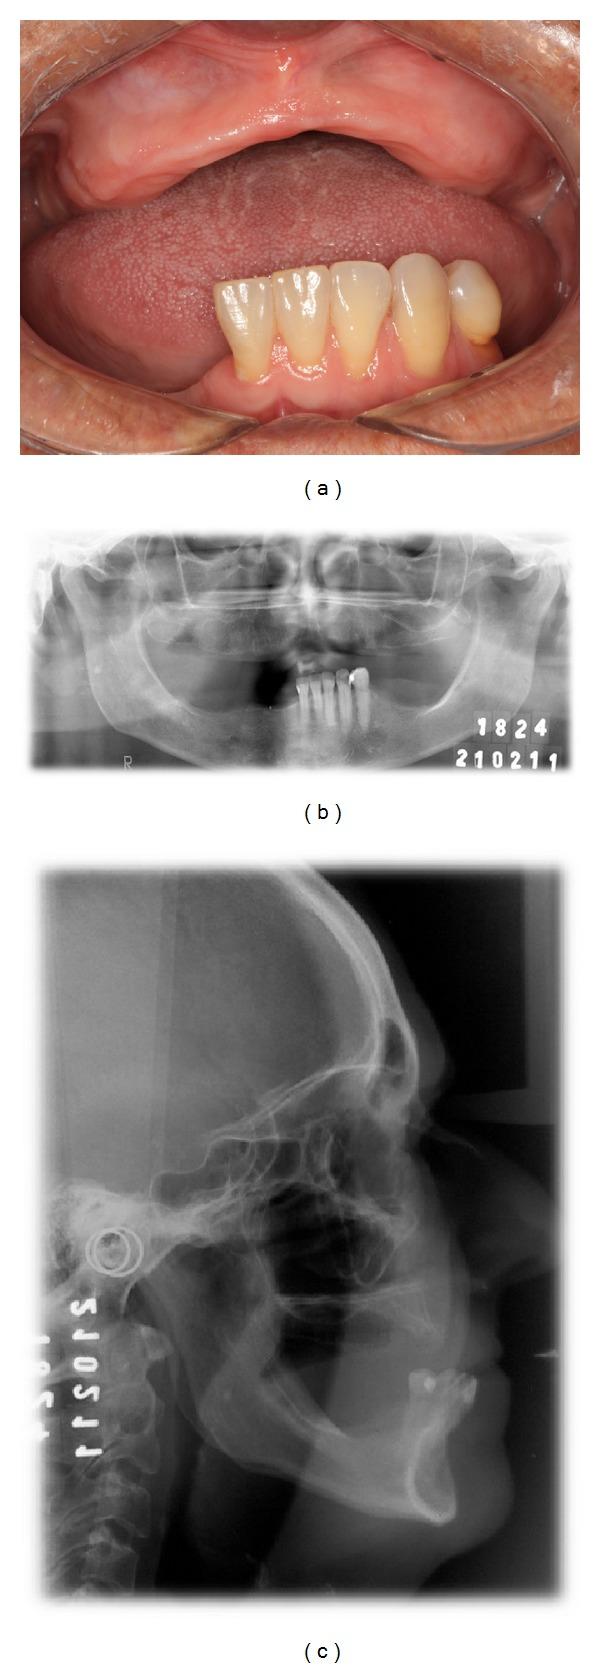

In mandibular edentulous patients, treatment based on immediate loading with rigid splinting in the mandible is well accepted; however, it is cost and time dependent, which sometimes limits this type of rehabilitation. To overcome these problems, the technique of immediate loading using a semirigid splinting extension system has been developed. Its advantages include low cost, technical feasibility, and reduced clinic time. This clinical report presents the applicability and the predictability of semirigid splinting of implants in the mandibular arch of an edentulous patient using a distal extension bar prosthesis system.

在下颌无牙患者中,基于下颌即刻负重并采用刚性夹板固定的治疗方法已被广泛接受;然而,这种方法成本较高且耗时,有时会限制此类修复方式的应用。为克服这些问题,已开发出使用半刚性夹板延伸系统进行即刻负重的技术。其优点包括成本低、技术可行性高以及临床时间缩短。本临床报告介绍了在一名无牙患者的下颌弓中使用远端延伸杆假体系统对种植体进行半刚性夹板固定的适用性和可预测性。